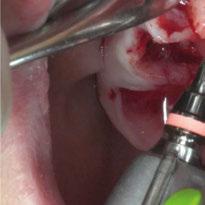

y lo que se pudo preservar del hueso malar. Se añadió una malla sinterizada infraorbitaria para dar volumen a la mejilla y se planificaron dos brazos de conexión que emergieran en las posiciones 24 y 26 de forma subgingival (Figuras 8 y 9). La superficie interna que apoyaba en el hueso era de titanio microrrugoso, y la superficie externa y conectores de titanio pulido y hexágono externo universal (Figuras 10 y 11). La cirugía se hizo bajo anestesia general en infiltración con anestesia local (4% articaína, 1:100.00 epinefrina), levantando el

colgajo cutáneo de la mejilla por vía intraoral, preservando el colgajo temporal para no comunicar con el remanente de la cavidad naso maxilar (Figura 12). Se emplearon 10 tornillos de osteosíntesis de 1,9 mm y la estabilidad primaria obtenida fue excelente (Figura 13)

Figura 13. Fijación del implante y emergencia de las conexiones.